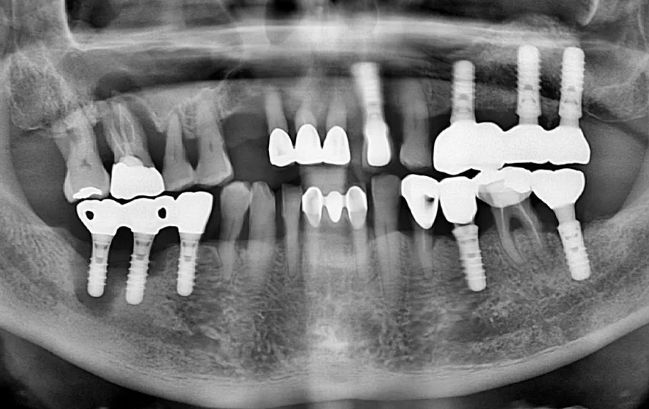

50대 남성, 원데이 수면 전체 임플란트 19개 식립